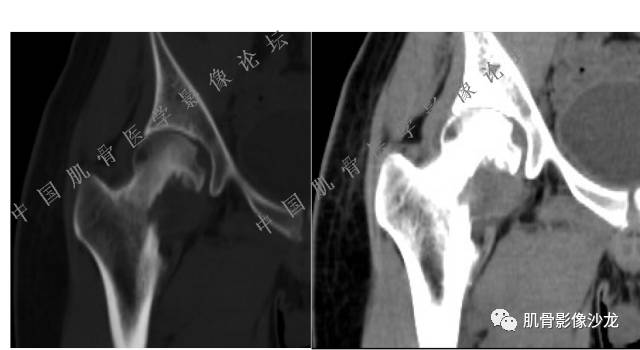

张小林 20:13 磁共振有双低信号,结合CT确实要考虑有纤维成份。

医影在线 20:13 干骺端溶骨性破坏,边缘模糊,低密度肿块,似有钙化

Echo 20:13 有骨质破坏,边界不清,有软组织肿块,我觉得恶性是要考虑的

Echo 20:16 软组织肿块突破了骨皮质

葛英霖 20:20 局部骨质有硬化,不能完全排除干扰

Echo 20:23 我个人觉得,17岁男性,病灶发生在原干骺端区域,溶骨性骨质破坏,似有肿瘤骨,有软组织肿块形成,从常见病发生率来说,骨肉瘤还是要考虑的

葛英霖 20:24 这个部位有一个需要鉴别的就是软骨母